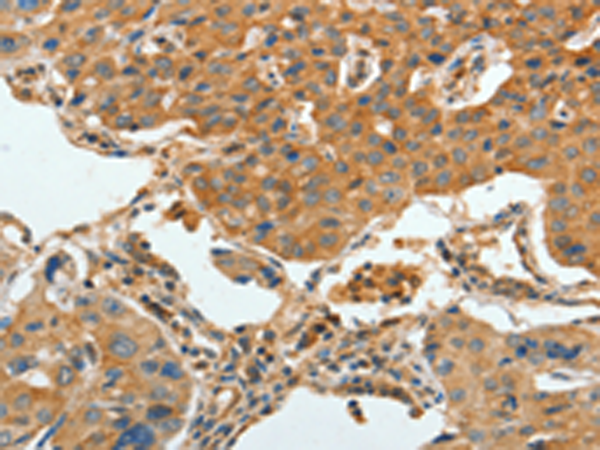

分类: 科研抗体货号: P07106别名: BBS3, RP55应用: IHC反应种属: Human, Mouse